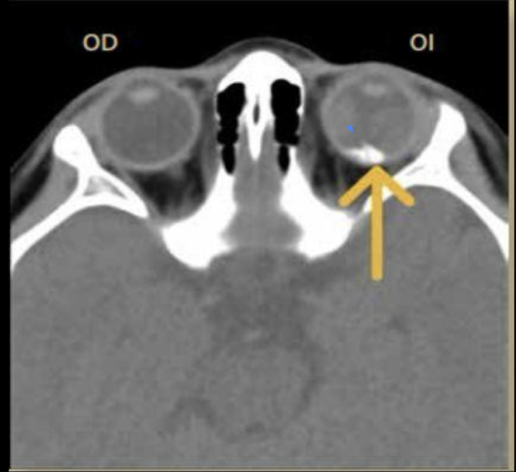

Clave en imagen para dx de retinoblastoma

• Calcificaciones intraoculares

¿Qué esperas ver en una TC por retinoblastoma?

• Calcificación “manchada” o punteada

• Capta contraste

• Tumor trilateral

¿de qué enfermedad nos habla la siguiente imagen?

Retinoblastoma trilateral